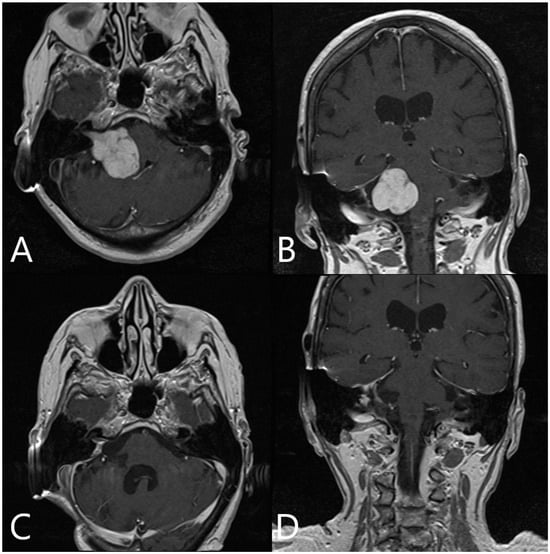

Illustrative Cases